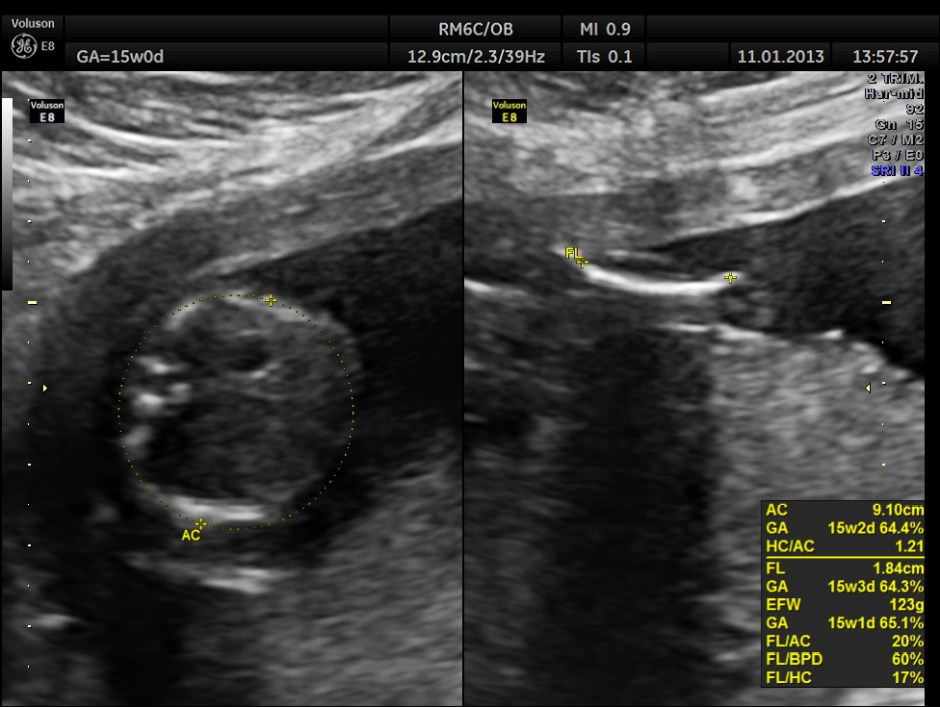

This was a 28 year old lady , primi gravida , who presented with acute lower abdominal pain . Her gestational age was around 15 to 16 weeks.

The pregnancy scan was otherwise normal.